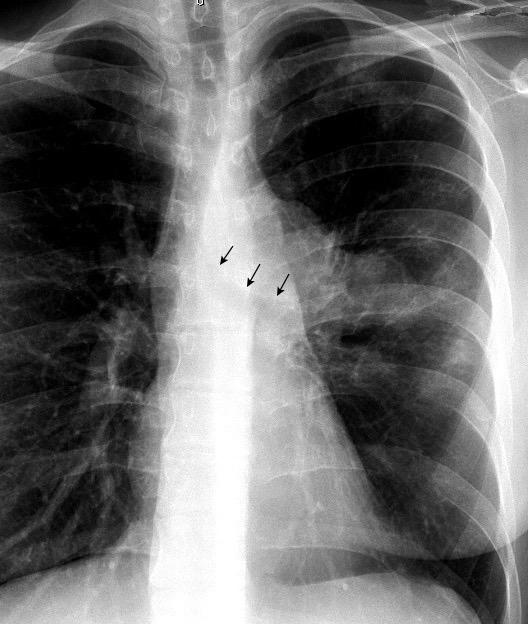

Anatomía

BPI: 75% de normales

La imagen es probable que represente al BPI, a la altura del nacimiento del BLSI.

AV,. The left lateral radiograph of the chest. Part One. Med. Radiogr. Photogr.1979.

La presencia de tumor o ganglios rodeando el BPI hace que este aparezca como mucho más nítido y definido.

Carcinoma microcítico..

Parálisis frénica. Atelectasia parcial de LSI.

Whitten CR. A Diagnostic Approach to Mediastinal Abnormalities. Radiographics 2007 / Marano R et al. Cardiac Silhouette findings And mediastinal lines and stripes. Chest. 2011